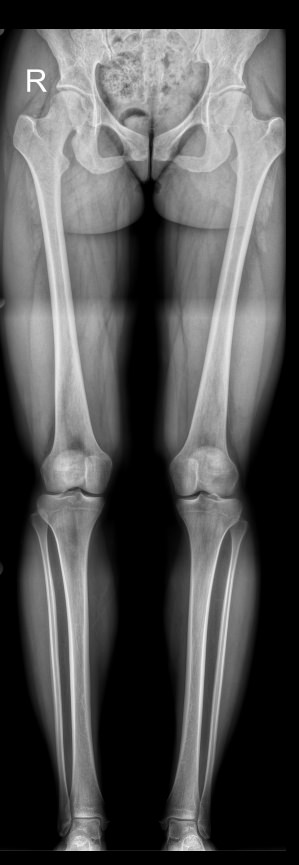

Из-за вертикального положения тела и необходимости перемещения на ногах именно на них приходится основная нагрузка. В результате нижние конечности имеют сложное строение, в котором важную роль играет взаимное расположение и пространственная ориентация отдельных элементов и сегментов. Для оценки движения в суставах, а также для планирования лечения разработаны референтные линии и углы, для определения которых используется длинномерная рентгенограмма или стичинг (Stitching). Это несколько прицельных снимков отдельных участков ног, собранные в один на экране компьютера.

С помощью стичинга на длинномерных снимках можно определить:

• Референтные линии и углы;

• Длину отдельных костей;

• Разницу в длине между правой и левой одноименными костями;

• Расстояние между идентичными точками на правой и левой ногах (при определении значения варусной и вальгусной деформации)

Подготовка не нужна. Для диагностики необходимо снять одежду с нижней половины туловища, оставаясь в белье, надеть защитный фартук и встать спиной к детектору. Стопы и коленные чашечки должны смотреть прямо, руки надо убрать за голову. Каждый раз рентгенолаборант помогает занять правильное положение. Если у пациента одна нога короче, подставляет под нее небольшую подставку.

Выполняется 3 снимка ног, включая таз, в прямой проекции, вам при этом не надо ничего делать. В некоторых случаях дополнительно требуются снимки в боковой проекции, при этом есть варианты: